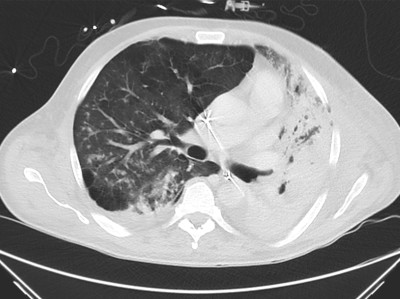

Ein 58-jähriger Krebspatient wird zur Behandlung einer AML stationär aufgenommen. Im Verlauf entwickelt er eine progrediente respiratorische Insuffizienz und muss schließlich invasiv beatmet werden. Erst nach fünf Wochen gelingt der Nachweis der zugrunde liegenden infektiologischen Ursache.

Komplikation bei AML – eine langwierige Ursachensuche

CT-Befund des Thorax/© Prof. A.- J. Lemke, Zentrum für Radiologie, Gesundheit Nord gGmbH, Bremen, mit freundlicher Genehmigung , Koloskopie/© Kzenon / stock.adobe.com (Symbolbild mit Fotomodellen), Thrombozytopenie/© Kreipe, H. / all rights reserved Springer Medizin Verlag GmbH, Echoarmen Lymphknotenmetastase ohne Mark-Rinden-Struktur im Ultraschall/© Wihlfahrt K et al. / all rights reserved Springer Medizin Verlag GmbH, Patientin schaut besorgt auf Infusionsbeutel/© KatarzynaBialasiewicz / Getty Images / iStock (Symbolbild mit Fotomodellen), Zytologie mit Plasmazellen/© David A Litman / stock.adobe.com, Mit Schuhen auf Körperwaage/© Africa Studio / Stock.adobe.com (Symbolbild mit Fotomodell), Histopathologischer Befund bei akuter myeloischer Leukämie/© National Cancer Institute/cancer.gov, Einer Frau wird eine Infusion gelegt/© stephm2506 / stock.adobe.com, Röntgenassistentin bedient Röntgengerät/© nicoletaionescu / Stock.adobe.com (Symbolbild mit Fotomodell), Frau hält Kapseln in der Hand/© diego cervo / stock.adobe.com, Kraniales MRT/© Dr. Müller-Abt, Kinderradiologie, Olgahospital Stuttgart (Mit freundl. Genehmigung, alle Rechte vorbehalten), Search Icon, Blutabstrich der chonisch lymphatischen Leukämie/© jarun011 / Getty Images / iStock, Endoskopische Befunde des Magenkarzinoms/© Probst, A., Messmann, H. / all rights reserved Springer Medizin Verlag GmbH, Hand hält Laborröhrchen/© Kunstzeug / stock.adobe.com (Symbolbild mit Fotomodell), Radiologin richtet Mammographiescreening ein/© LIGHTFIELD STUDIOS / stock.adobe.com (Symbolbild mit Fotomodellen)